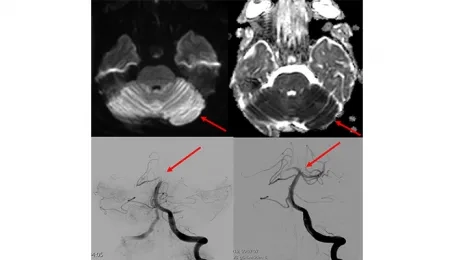

If stroke symptoms have not gone away for more than 6 hours, and if a blockage is detected in one of the main arteries in the brain, interventional radiology comes into play at this point. In the angiography unit, small pipes (catheters) are placed to the clot in the occluded artery in the brain by entering through the groin or the wrist, and the clot is mechanically removed and the blood flow in the occluded artery is restored to normal. When we look at the literature, it has been shown that mechanical removal of the clot, even in periods up to 6-24 hours after the emergence of stroke symptoms, allows the patient to continue his/her life independently or less dependently.

If the acute stroke is treated early, it becomes possible for patients to continue their lives without any disability or addiction. Some of our patients who come with sudden paralysis and speech disorders start to move their arms and legs after the clot is removed while they are still on the angiogram table, and their speech improves, they ask us questions, answer our questions, and return to work within a few days. These situations and moments we encounter in treatment are really pleasing.